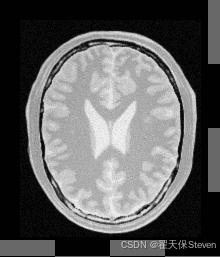

过程图像如下:

固定图像

浮动图像